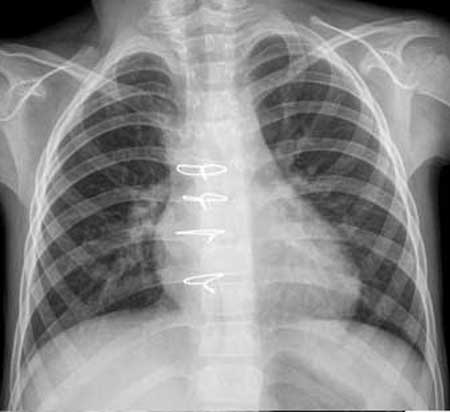

以下是引用听蝉观竹在2007-2-12 1:22:00的发言:[br]1、肺血增多-----提示有血液左向右分流;常见有房缺、室缺、动脉导管未闭。[br]2、肺动脉段突出,心尖圆隆,右前斜位肺动脉圆锥隆起------右心室增大,而左心室不增大;室缺、动脉导管未闭虽然可以右心室增大、肺动脉段突出,但同时左心室也增大,符合者就剩下房缺了。[br]3、手术前右前斜位吞钡食道压迹加深,正位片右心缘第二弓明显增大-----有心房增大。手术后右心缘第二弓正常,说明右房压力正常。[br]4、主动脉结明显缩小-----这是房缺的特征表现。[br][br]虽然没有告诉心脏杂音的性质位置,根据影像分析-------房间隔缺损。重要的一点:房缺在透视下肺门“舞蹈”明显,比其它左向右分流先心更显著。[br][br][本贴已被 听蝉观竹 于 2007-2-12 1:34:56 修改过]